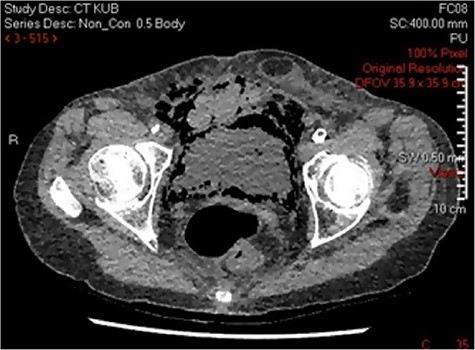

Three days post-procedure, the patient was confused and developed frank haematuria with a fall in haemoglobin from 124 to 107 g/L. A computed tomography (CT) scan of abdomen and pelvis demonstrated severe EC with abundant gas tracking outside of urinary bladder into the extraperitoneal space, extending to the anterior abdominal wall and inguinal orifice on the right, and obturator foramen on the left (Fig. 2). The urology on-call team recommended catheterization and treatment with empirical intravenous Piperacillin with Tazobactam for 5 days. A septic screen was undertaken including, blood tests and urine, wound, sputum and blood cultures. Klebsiella pneumoniae has cultivated in the urine culture, and subsequently, the microbiologist advised on converting drug regime to oral Trimethoprim based on culture sensitivities. The patient was discharged on the completion of the 14-day course of antibiotics.

Differentiation of EC from other conditions is mainly via X-rays, ultrasonography, and CT scan. Radiographic findings of EC include speckled areas of high radiolucency in the zone of the urinary bladder, which changes with the patient’s position. The air in the bladder wall may visualize as a “beaded necklace” appearance denoting irregular thickening of the non-dependent mucosal surface [10]. Ultrasonography can exhibit echogenic gas within the bladder wall with a dark shadowing artefact [10]. CT scans permit early detection of intraluminal/intramural gas. It assists in detecting the severity and extent of the condition in addition to evaluating other causes of intraluminal gas [2–4, 8–10]. CT scanning is the most preferred and accurate diagnostic imaging technique for this condition.